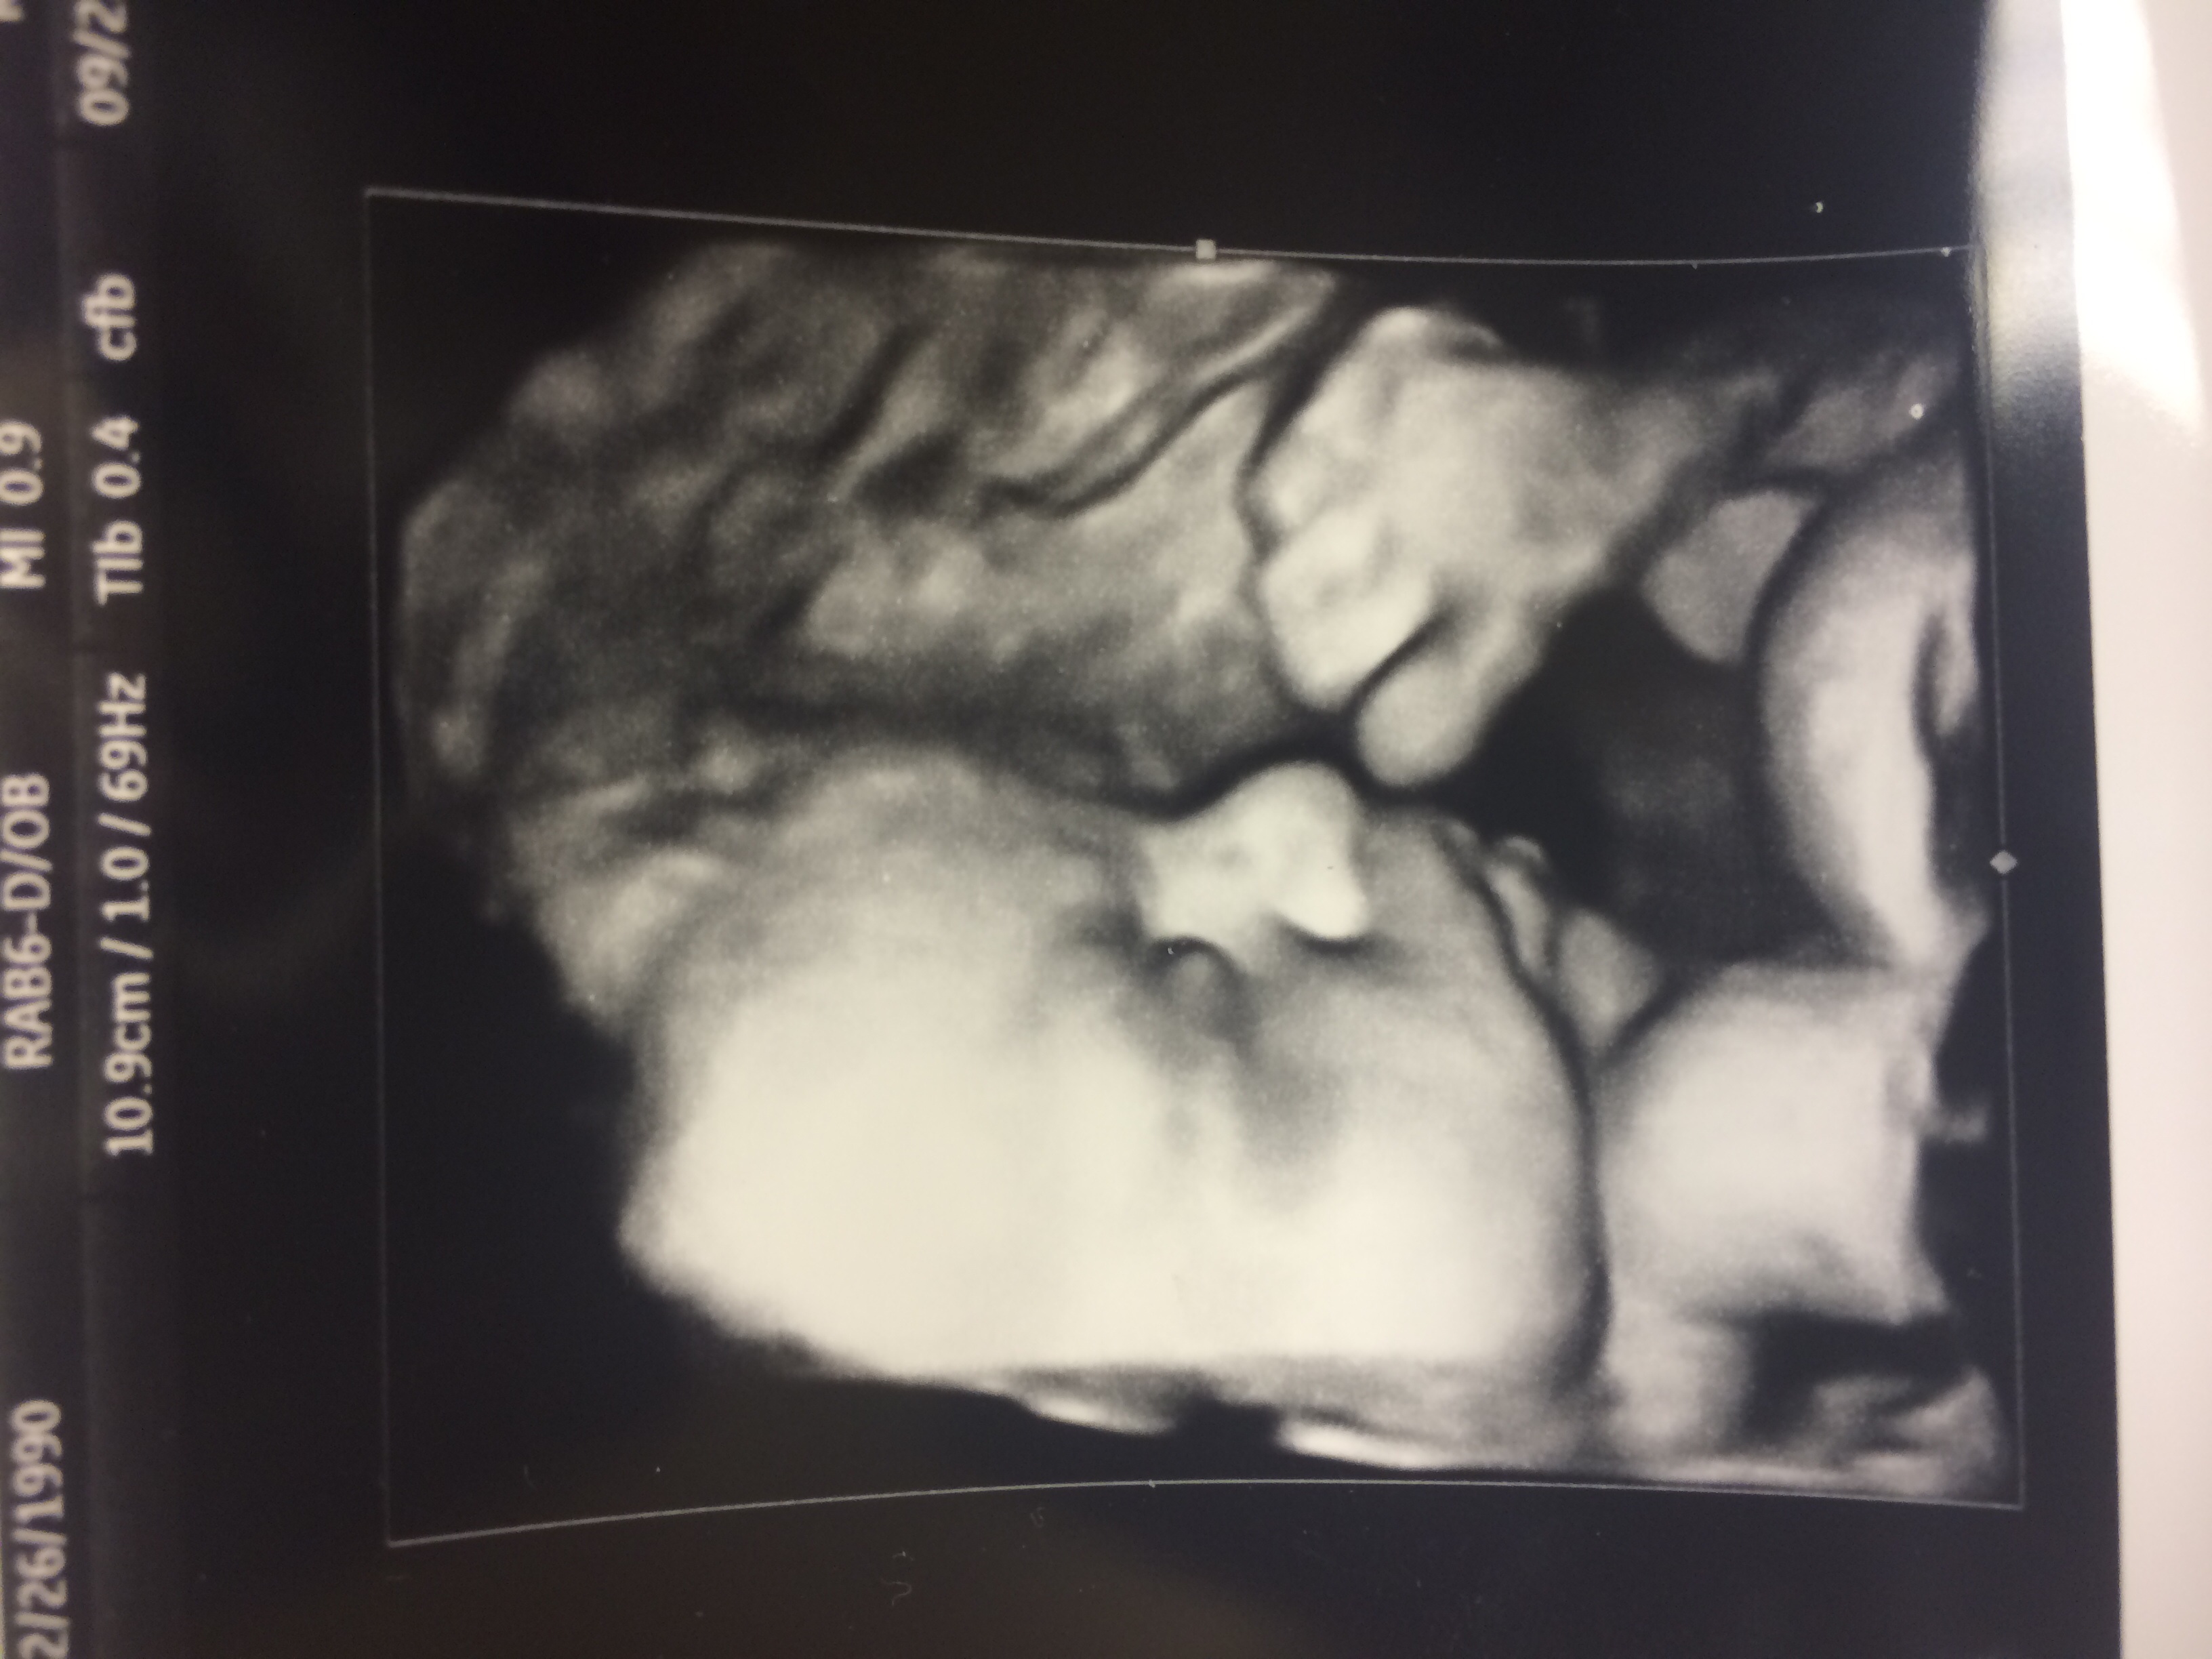

30 week scan - 4.2 pounds (estimated, obviously!). 75th percentile. Measuring 2 weeks early.

At my 20 week scan I didn't hear anything about weight, but baby was in 50th percentile.

Ok, SO...we had a scan at 32+5 & they said that his head was measuring right on but that his torso and femur was a little on the small side. He was 3lb 11oz and in the 21st percentile. When I got back to my hospital room I asked one of the nurses what the percentile even meant and she told me that was a question for the doctor because they could explain it better and then that Dr. never came lol SO....what does that mean exactly?

I got some steroid shots to help baby grow and develop so hopefully he grows to be a big boy